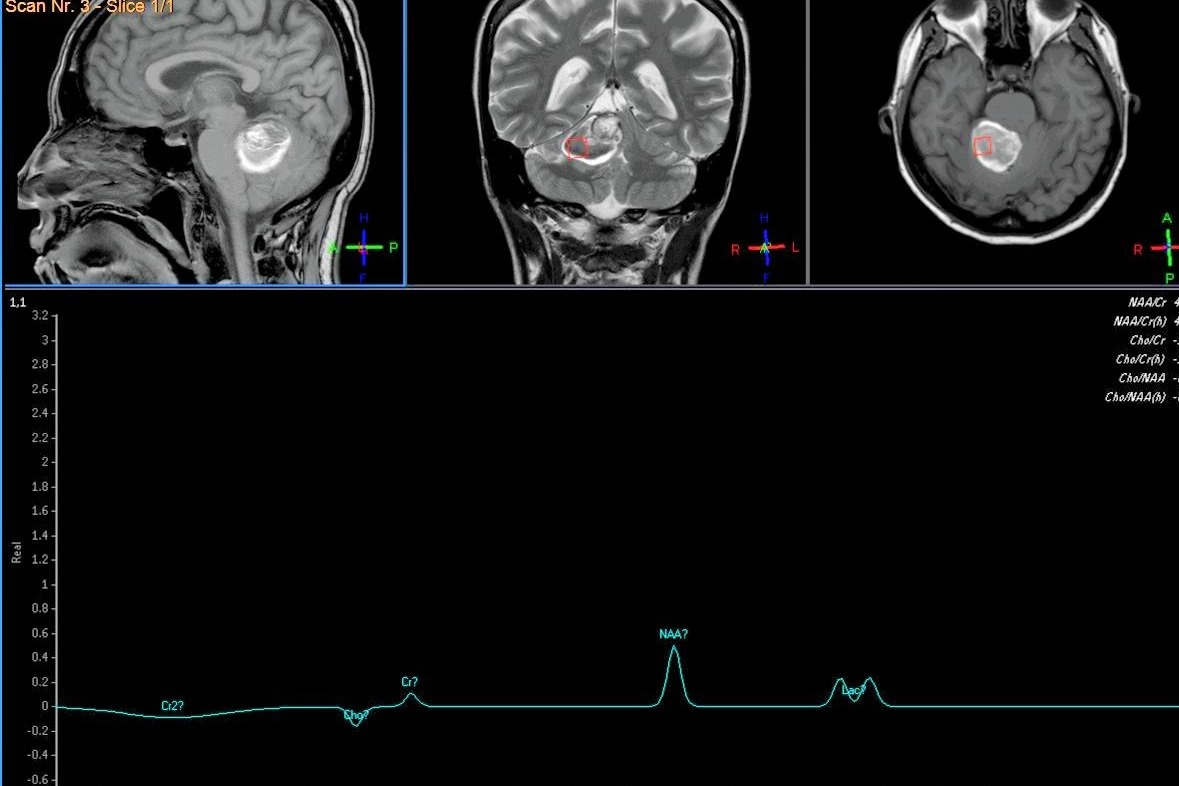

The disease crept up unexpectedly. On May 20th, Veronica started feeling dizziness, fatigue, loss of voice, and vomiting after consuming food. To date, Veronica needs constant assistance as she lost balance and control of her body while walking or doing any vital life activities. All those symptoms and reactions of the body she experiences made her see doctors and do tests to find out what is wrong. TAC and MRI scans show some anomaly in Veronica's brain. The Doctors are not sure yet of what is going on. The surgery is imperative to remove the discovered anomaly, determine what it is, and what are the further steps. The first Lab and Test was already expensive, and now she faces even more expensive Surgery, Hospital, Recovery, Therapy, etc. Since Covid-19, she doesn't receive any income to pay for the surgery, further treatment, and recovery process.

Marked red is the found anomaly to remove.